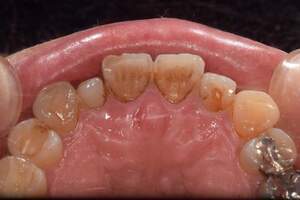

歯石除去、着色除去

治療前

治療後

| 年齢 | 25歳・女性 |

| 主訴 | 主訴:歯石除去、着色除去 治療部位:全顎 |

| 治療内容 | 初診検査・歯石除去・PMTC |

| 治療期間 | 60分 |

| 費用 | 合計約10,500円 初診検査約3,000〜4,000円 歯石除去約1,000円 PMTC5,500円(自費診療) (2024年6月現在) (歯の本数や検査内容で料金が変動します。) |

| リスク・副作用 | ・歯ぐきの炎症がある場合は歯石除去中に出血を伴う可能性があります。 ・処置後、知覚過敏が起こる可能性があります。 ・歯ぐきの炎症が治ると、歯ぐきが引き締まる為歯が長くなったと感じる事があります。 ・PMTCは歯を白くするものではなく着色・バイオフィルムの除去を目的としています。 |

| 治療方針 | 全顎的な歯石除去後、PMTCで着色とバイオフィルムを除去。 |

| 特記事項 | 矯正経験あり ホワイトニング経験あり |

| 担当者所見 | 歯石除去と前歯部の着色除去希望で来院されました。 下顎前歯の歯間部の歯石に対してフロス指導を行いました。 PMTCにより着色がなくなり、歯のトーンアップも感じられたと喜んでくださいました。 |